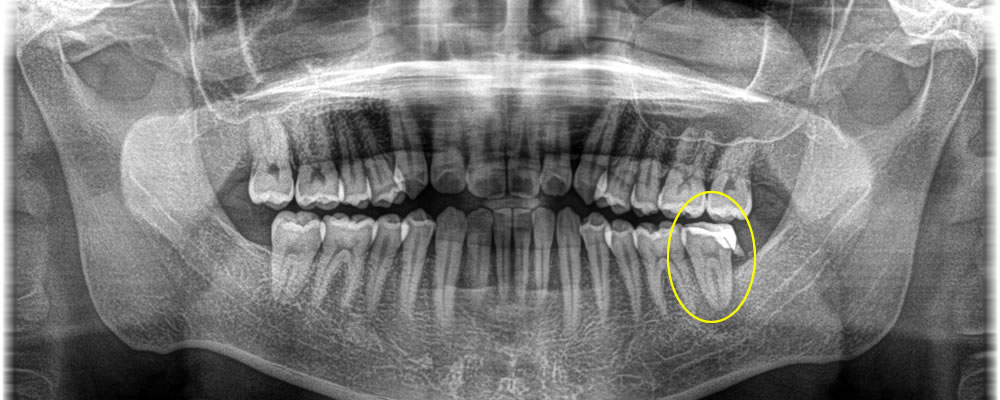

根破折で根の先端に膿がたまっているため抜歯しインプラントで修復した症例

年齢

60代

性別

女性